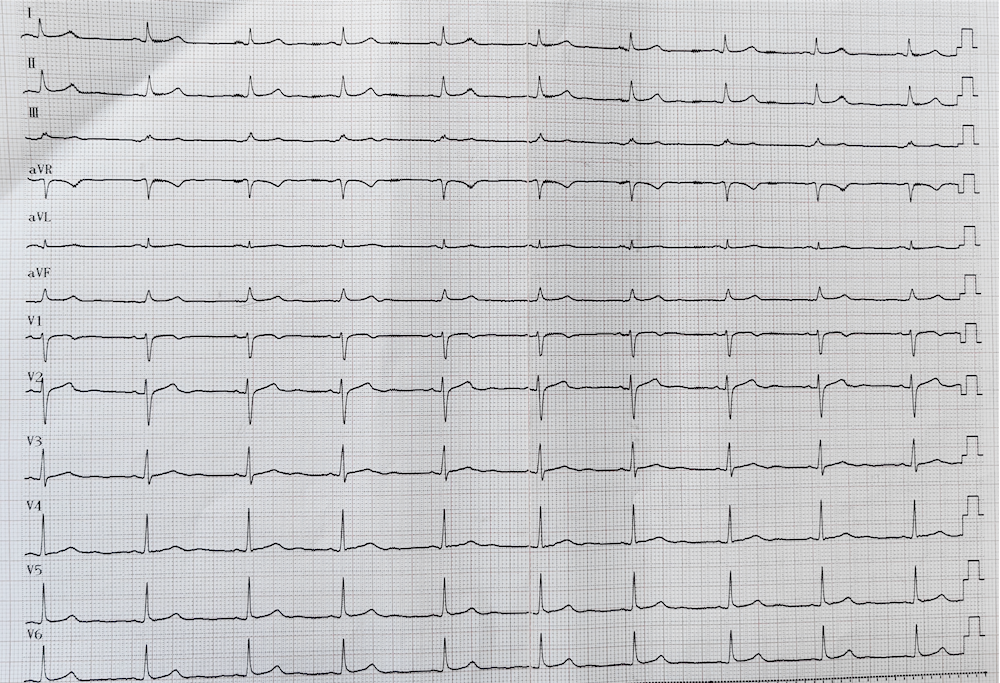

患者术前心电图

患者术后心电图

11月1日,刘启明教授与湘雅二医院桂林医院心内科副主任赵印平在局部麻醉下为患者进行手术。周先生为右室流出道室早、室速,在三尖瓣瓣上、瓣下均有异位节律点,射频消融存在一定难度,极其考验施术者的手法。刘启明教授在不到两小时的时间就顺利完成手术,术后患者立即恢复窦性心律,于11月3日康复出院。周先生和家属感激地说:“感谢国家的好政策,感谢国家区域医疗中心,才有国内知名教授来桂林给我们做手术!”